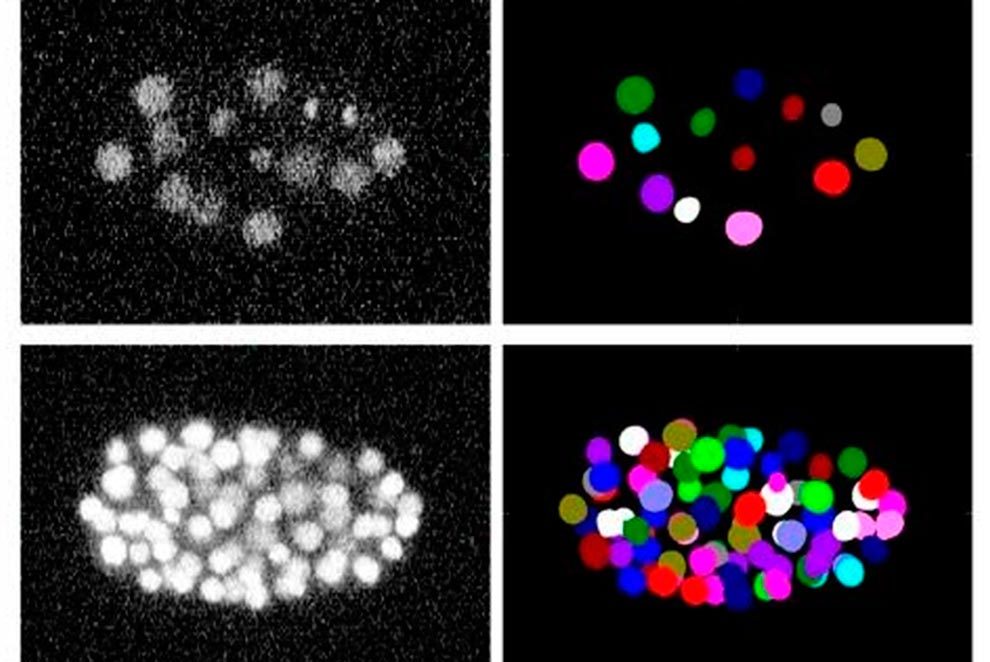

En total, se han analizado 52 vídeos que ocupan 92 GB. Algunos son sintéticos, es decir, creados mediante un software que simula las células, mientras que otros son reales, obtenidos fundamentalmente mediante microscopía bidimensional y tridimensional.

El trabajo publicado en Nature Methods resulta útil para investigadores que utilizan los métodos de seguimiento celular en sus trabajos. Todo el material utilizado en el Cell Tracking Challenge puede servir como una guía que ayude a tomar decisiones sobre qué solución algorítmica utilizar en los diferentes casos, consiguiendo así extraer información más precisa que contribuya a hacer avanzar el conocimiento en el campo biomédico.